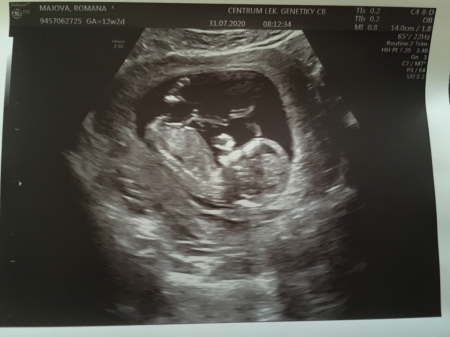

4. Jak vypadá miminko 12. týden těhotenství?

Plod měří na konci tohoto týdne od temene k zadečku asi 6cm, váží asi 10-13q.

Plod stáří 11+2 týdne a velikosti 47 mm. Je vidět hlava s nosem, jasnější horní a dolní čelistí. Vpravo pak dolní končetiny.